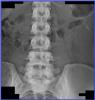

Consideraciones especiales: Controlar la tensión arterial antes del tratamiento, realizar examen físico y estudios de laboratorio de rutina. hemograma completo, electrolitos séricos y hepatograma, ECG.